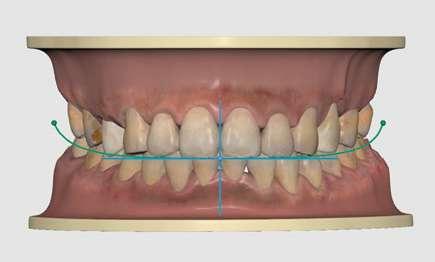

2. Análisis intraoral (Ilustración 2 y 3):

 Clase III molar y canina de Angle bilateral.

 Mordida abierta anterior > 3 mm.

 Compresión maxilar junto con mordida cruzada posterior bilateral.

 Línea media inferior desviada 2 mm hacia la derecha.

El objetivo principal de este tratamiento fue la corrección de la discrepancia maxilar transversal esquelética (> 5 mm), seguida de la corrección vertical y sagital, para lograr una relación oclusal funcional y estable (10).

Plan de tratamiento y progreso

Se informó al paciente sobre varias opciones de tratamiento, incluyendo la cirugía ortognática combinada con ortodoncia. Sin embargo, el paciente optó por no someterse a cirugía. En consecuencia, tras realizar la extracción de los terceros molares y el tratamiento

4

de las caries existentes, se optó por un plan de tratamiento ortodóncico compensatorio utilizando MARPE, seguido de alineadores transparentes.

Objetivos del tratamiento:

1. Expansión del maxilar mediante MARPE, corrigiendo la mordida cruzada y la deficiencia transversal.

2. Cerrar la mordida abierta anterior mediante extrusión controlada de incisivos.

3. Establecer una relación molar y canina funcional.

4. Optimizar la alineación y la estética dental con alineadores.